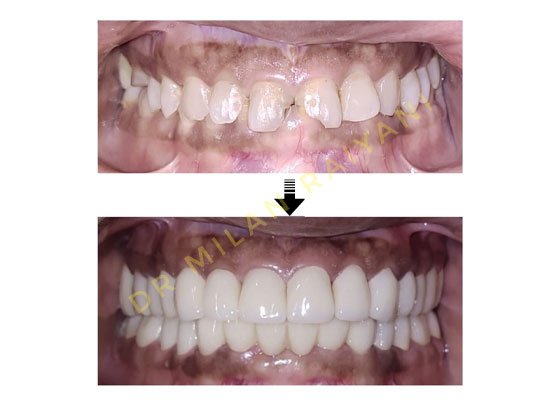

GALLERY